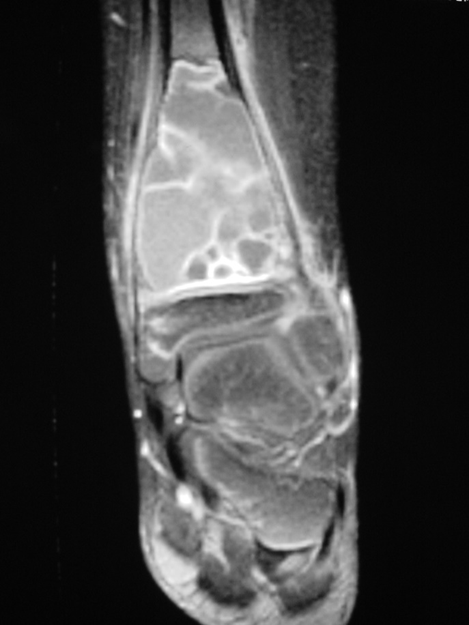

MRI

- Geographic well circumscribed

- High signal on T2 weighted MRI images

- Fluid/Fluid level (T2) are highly characteristic

Fig 2 a-e. MRI of an ABC of Distal Tibia: Fig 2 a-c: geographic cystic expansile lesion with fluid-fluid levels. The fluid-fluid levels are caused by bleeding into the cavities. The blood collects and the degredation products settle to the gravity dependent areas of the cavities. This shows up as fluid-fluid levels on the MRI. Fig 2 d,e: This is a gadolinium enhanced MRI of the ABC of the distal tibia. There is peripheral and septal enhancement indication cyst formation. The contrast outlines the cystic cavities but does not enter into the center